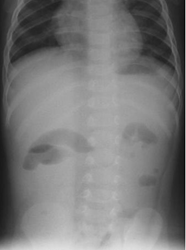

In paralytic ileus, there is too much gas in both small and large bowels (Figure 4 & 5).

Figure 5 Anteroposterior supine abdominal radiograph in a 9-month-old infant with abdominal distention following diarrhea showing dilatated bowel loops with smooth walls scattered throughout the abdomen haphazardly with presence of gas in the rectum suggestive of paralytic ileus.